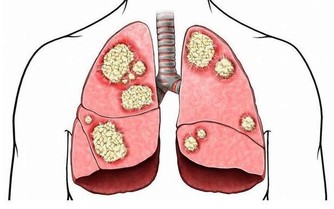

幽門螺桿菌主要潛伏在胃粘膜組織中,人一旦感染這種細菌,就可能引起口臭、胃炎,甚至是胃癌。